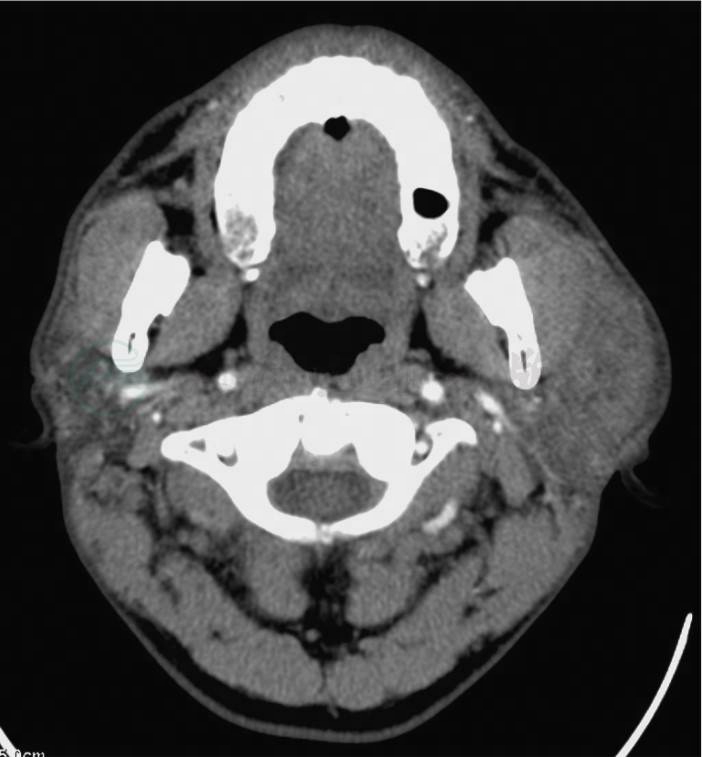

腮腺和面颈部淋巴结是嗜酸性粒细胞淋巴肉芽肿的好发部位。腮腺咬肌区嗜酸性粒细胞淋巴肉芽肿可合并皮肤或皮下组织同时受累。影像学上,嗜酸性粒细胞淋巴肉芽肿的病变形态一般有两种表现:弥漫状和类圆形肿块。腮腺、皮肤或皮下组织的嗜酸性粒细胞淋巴肉芽肿多呈弥漫性肿块表现,边界模糊。淋巴结病变则多呈类圆形肿块形态,边界较清晰。

CT 表现:病变多为软组织密度表现(图2);增强CT上,病变实质部分可无明显强化或为轻度至中度强化表现,但病变边缘可呈环形强化表现。

图2 嗜酸性粒细胞淋巴肉芽肿

增强CT横断面示左腮腺较对侧明显肿大,内有弥漫增生的异常软组织密度影,边界不清